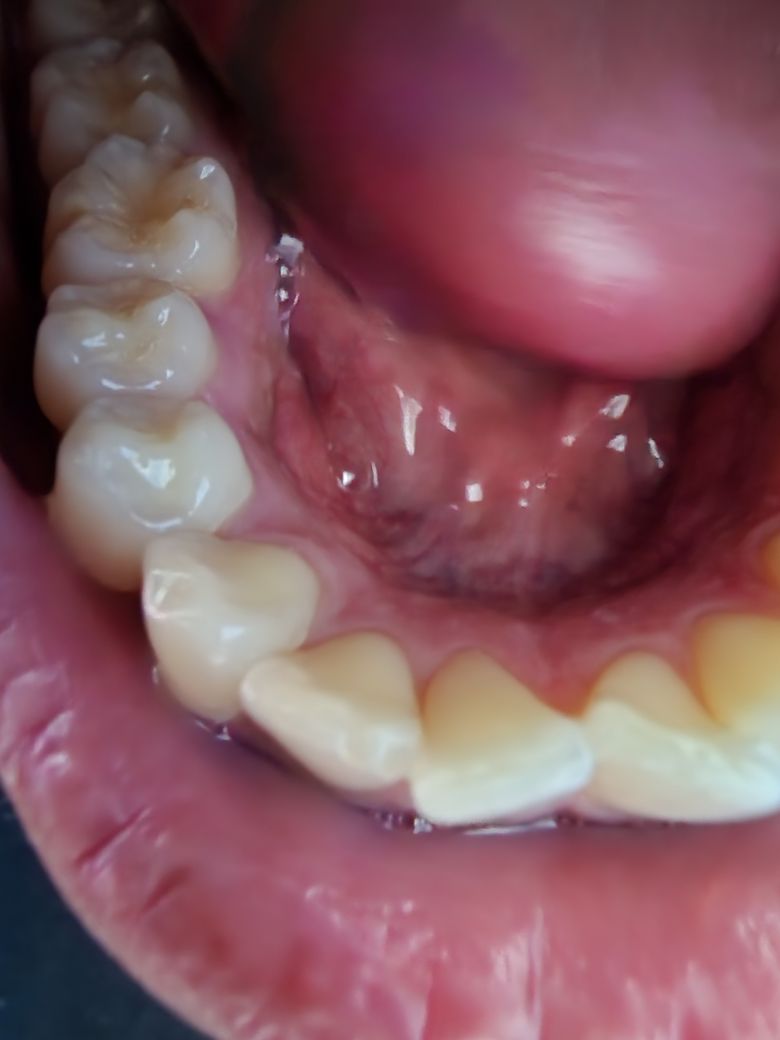

쇠 젓가락을 씹었는데 치아가 깨진건가요?

치킨을 허겁지겁 먹던중

부끄럽게도 쇠젓가락을 씹어버렸습니다

사진상으로는 정확한 판단이 어렵지만 치아에 금이 갔을 가능성이 매우 높아 보입니다. 즉 파절이 되지 않아도 해당 치아에 금이가게 되면 시린 증상과 더불어 저작시 상당한 통증이 나타날 수 있습니다. 보통 이러한 경우에는 특별한 통증이 없더라도 치과 방문 후 해당 치아에 대한 평가를 받아보는 것이 좋습니다.

치아가 살짝깨지신거 같습니다. 범위가 크지는 않아서 치료는 안하셔도 될것같지만, 날카롭다면 치과에 가셔서 부드럽게 다듬으셔야될수도 잇습니다.

사진으로만 봤을 경우에는 파절된것이 맞아 보입니다.

치아가 미세하게 파절이 되고 통증등이 없다면 큰 문제가 발생하지는 않습니다.

하지만 파절이 될 정도로 강한 힘을 받았을수 있기 때문에 치아의 다른 부위에 손상이 있지 않을지 확인을 하기 위해서 치과에서 진료를 받아보는것이 좋습니다.